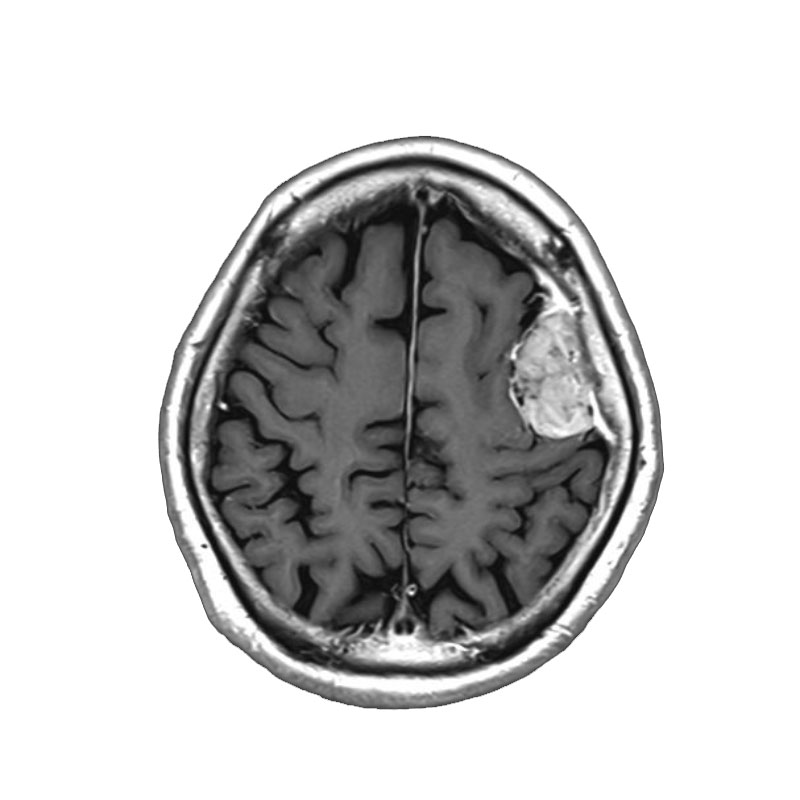

脳室内腫瘍

摘出術

北野/濵田